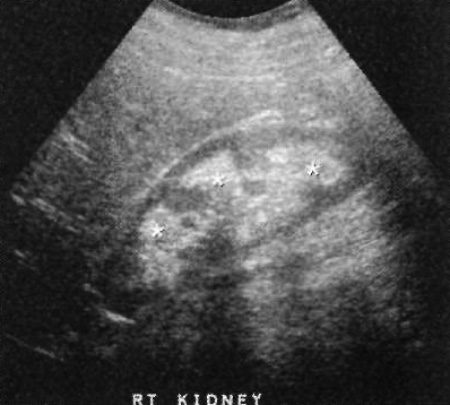

Ультразвуковая картина нефрокальциноза характеризуется наличием эхогенного очага в проекции коркового вещества (при корковом нефрокальцинозе) или в проекции пирамид мозгового вещества (при мозговом нефрокальцинозе). Отметим, что при незначительной кальцификации ультразвуковая тень не возникает (фото 11).

Фото 11. Мозговой нефрокальциноз. Ультразвуковое изображение в продольной проекции: пирамиды (отмечены звездочками) светлые, как почечный синус (в норме пирамиды гипо- или изоэхогенные по отношению к паренхима)